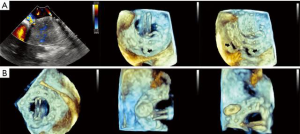

- Echocardiography, transthoracic (TTE) or transesophageal (TEE), is indispensable for diagnosis, procedure planning, intra-procedural guidance, monitoring complications and for patient follow-up. It is the imaging modality with the highest temporal resolution, adequate spatial resolution and the only one that can provide complete hemodynamic data. Several comprehensive reviews detail imaging protocols dedicated to mitral valve, as well as patient selection criteria for mitral procedures (3-5). Echocardiography can easily distinguish between degenerative and functional mitral regurgitation (DMR and FMR, respectively). DMR is a disease of the valve, which undergoes myxomatous degeneration, affecting the morphology and function of various structures: leaflet thickening, redundancy, prolapse and disjunction, or chordal rupture with a flail leaflet (Figure 2, Video 1) (6). DMR associates severe annulus dilatation, with a highly eccentric regurgitant jet that peaks at end systole and is oriented away from the diseased leaflet. In contrast, FMR is a disease of the ventricle, where a tethered or apically displaced papillary muscle impairs the closure of an otherwise morphologically normal valve, followed by annular dilatation. The FMR regurgitant jet peaks in early systole, is less eccentric and is oriented toward the culprit leaflet. Arguably, the severity criteria for FMR versus DMR may be different (5,7). The regurgitant jet volume is influenced by intravascular volume and left ventricular afterload. This explains the significant changes in MR severity assessment between interval examinations. TEE tends to overestimate MR severity, compared to TTE, if only a semiquantitative assessment of color Doppler is used. MR evaluation should be performed only during euvolemic state, keeping the recommended Nyquist limits for color Doppler (50–60 cm/sec) and proximal isovelocity surface area (PISA) measurements. Quantitative methods may overestimate highly eccentric or non-holosystolic jets. Gross errors commonly result from analysis of single frame color Doppler images, ignoring the dynamic changes of the regurgitant orifice area and jet volume. Lastly, the angiographic classification of MR severity does not overlap the echocardiographic severity grading. As none of the echocardiographic techniques fully characterizes MR, the proper evaluation of this condition requires considerable skill and experience. Mitral stenosis (MS) severity is largely based on valve area, with a threshold of 1.5 cm2, as transmitral gradients are highly variable and related to the heart rate and transmitral flow. While such a simplification is appealing, relying on valve area only may lead to inappropriate clinical decisions. Area measurement is prone to technical errors, using only planimetry of 2D cross sectional views, 3D ventricular views of leaflet edges, or 3D atrial views of the funnel shaped, calcified valve, where clearly defined measurement points are lacking. It is important to understand the difference between the geometric valve area resulting from planimetry and the smaller effective area of Doppler based methods: pressure half-time and continuity equation. In patients with symptoms out of proportion to TTE findings, supine bicycle exercise echocardiography reveals increased, exercise-induced mitral gradients and pulmonary systolic pressure, correlated with stress induced symptoms, even in the presence of a valve area >1.5 cm2 (8). Definition of device success in mitral procedures relies on criteria published by the Mitral Valve Academic Research Consortium (MVARC): reduction of MR to < moderate, transmitral gradient <5 mmHg, effective valve area >1.5 cm2, and LVOT gradient <20 mmHg (9). These parameters are measured 30 days post-procedure to allow for left atrial remodeling and functional recovery. One must again remember the difference between geometric and effective areas, which is more pronounced for the slit-like orifice of mitral stenosis, compared to the more rounded orifice of a TMVR device.

- Edge to edge repair. MitraClip® technology replicates the Alfieri edge-to-edge stitch repair of MR and is exclusively driven by echocardiography (Figure 9, Video 3). It has been used in >50,000 patients, with FDA approval limited to DMR as a class IIb indication in patients with prohibitive surgical risk. It achieves MR reduction and may preclude surgical repair in failed cases (5). The echocardiographic patient selection criteria and the intraprocedural guidance principles have been extensively described (5,27,28). Experienced operators commonly obtain patient, procedural and technical success, with acceptable device success, as defined by MVARC (9). The long-term hemodynamic impact of MitraClip® implantation has been less enthusiastically studied. Echocardiography-based mitral valve sizing and regurgitation quantification relies on several assumptions: single, static, rounded regurgitant orifice and single, central, non-eccentric, holosystolic jet, without associated MS. Post-clip deployment, these assumptions are violated, as a double orifice is created, frequently accompanied by two regurgitant jets. Area measurement of the double orifice is limited to the planimetry of cross-sectional views. A definition of MS post MitraClip® patients does not exist; a pressure halftime of >91 m/sec was found to correlate with high post-procedural gradients. Post-procedural mitral gradients are difficult to predict. Typically, they are mildly elevated compared to baseline and tend to not increase proportional to the number of clips implanted, even at higher heart rates, but raise significantly with exercise echocardiography. The residual regurgitation evaluation is limited to semi-quantitative color Doppler data, as PISA method is not validated for double orifices and jets. The impact of a persistent interatrial defect and shunt is not well understood and closure is advocated in patients with pulmonary hypertension and failing right ventricles. Notably, recent data shows absence of post implant LV remodeling in patients with LVEF <40%, in contrast with earlier reports (29). Imaging MitraClip® patients remains largely operator-dependent requires development of specific criteria to clearly define device success and complications.